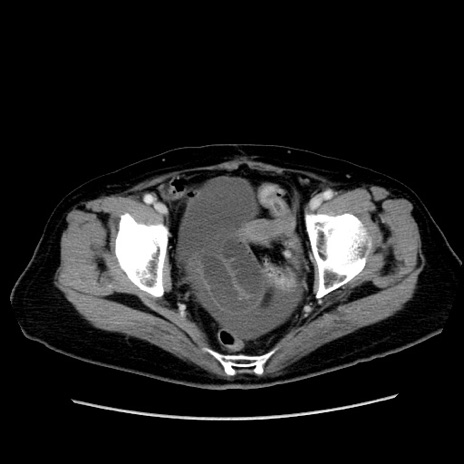

症例19(横断像)

【症例】80歳代女性

【主訴】下腹部痛

【現病歴】約8時間前より下腹部痛の出現あり、救急外来受診。

【既往歴】両側付属器切除

【身体所見】意識清明、下腹部正中に手術痕あり、その部位に一致して圧痛と反跳痛あり。腸蠕動音は亢進。

【データ】WBC 9300、CRP 0.15